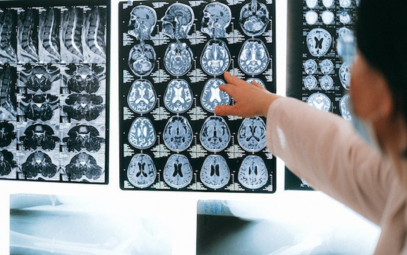

NEWS: Holding Prescribed Aspirin in Chronic SDH Receiving Burr Hole Evacuation May Not Decrease the Risk of Recurrent SDH Requiring Surgical Intervention at 6 Months

Background: There is uncertainty regarding whether aspirin should be continued in patients with chronic subdural hematoma (cSDH) who undergo surgical evacuation. The risk of bleeding in the setting of aspirin use should be weighed against the risk of cardiovascular events in the setting of...